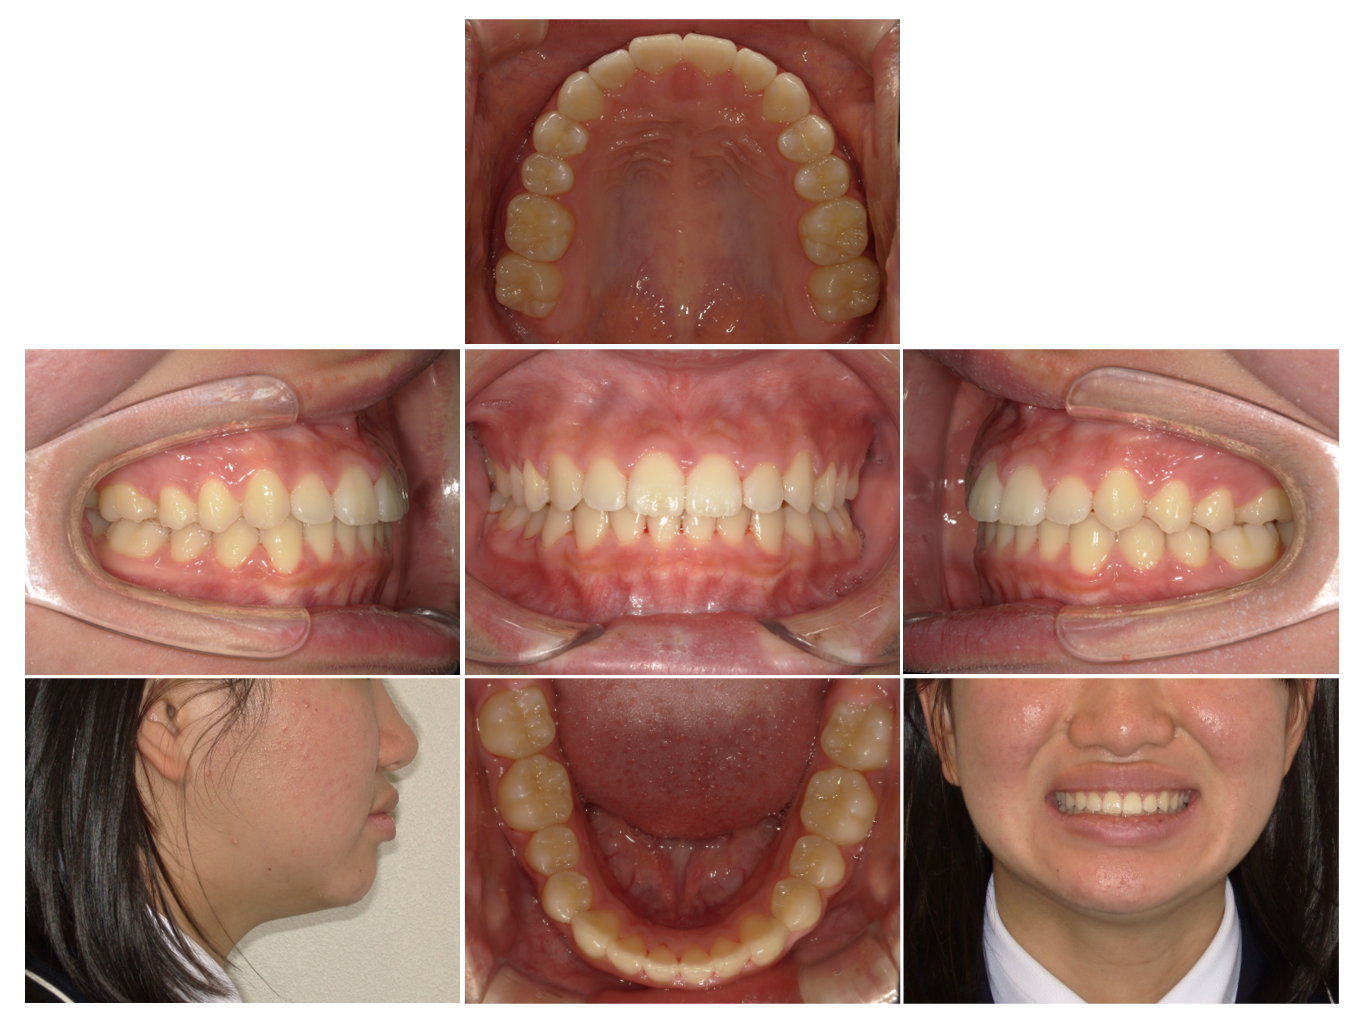

症例1

| 来院時の主訴 |

全体的なガタガタを治したい。

できれば抜歯はしたくない。

歯並びを気にせず笑えるようになりたい。

| 医院での対応や適用装置 | マウスピース矯正装置を使用して主訴であるガタガタを改善しました。 ガタガタの改善に必要なスペースの確保のために上あごの親知らずのみ抜歯を行いました。 |

| 通院期間 | 1年1ヶ月 |

| 通院回数 | 7回(治療中) |

| 治療費用総額 | 725,000円(税込) |

| リスクと副作用 | 矯正治療による歯の移動に伴う痛み、歯根吸収、虫歯 |